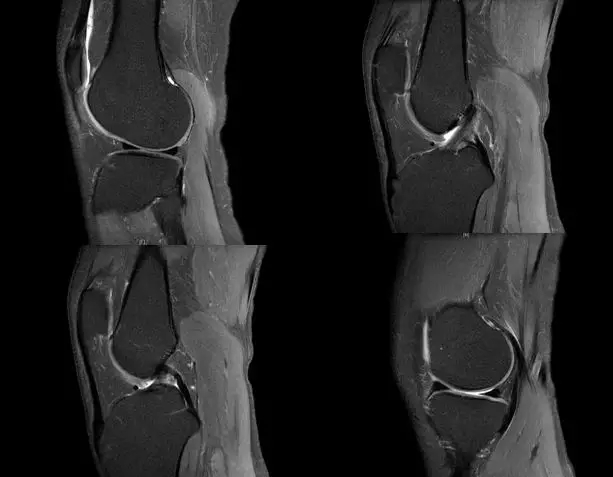

磁共振扫描在关节运动损伤诊断中的应用

关节扭伤常常导致膝关节相关韧带结构的损伤,如何及时发现这些损伤并进行相关的治疗,是我们临床医师常常面临的问题,除了相关病史、临床体征之外,磁共振扫描也是重要的诊断依据

膝关节的解剖结构

正常的膝关节

韧带结构:形态,张力,质地,连续性

半月板:完整性,形态,质地

Blumensaat 角(-1.6度)

大于9-15度视为异常

前交叉韧带与胫骨平台角度(56度)

小于45-50度视为异常

后交叉韧带折弯度

弧度:0.19厘米,角度:114-123度